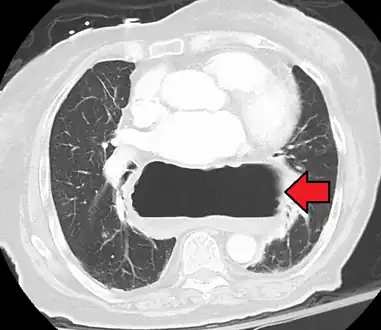

The diagnosis of a hiatal hernia is typically made through an upper GI series, endoscopy, high resolution manometry, esophageal pH monitoring, and computed tomography (CT). Barium swallow as in upper GI series allows the size, location, stricture, stenosis of oesophagus to be seen. Besides, it can also evaluate the oesophageal movements. Endoscopy can analyse the esophageal internal surface for erosions, ulcers, and tumours. Meanwhile, manometry can determine the integrity of esophageal movements, and the presence of esophageal achalasia. pH testings allows the quantitative analysis of acid reflux episodes. CT scan is useful in diagnosing complications of hiatal hernia such as gastric volvulus, perforation, pneumoperitoneum, and pneumomediastinum.[8]